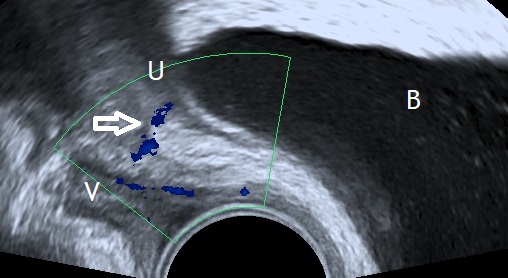

The following images represent an abnormal passageway between the ureter and the vaginal apex following a complicated hysterectomy.